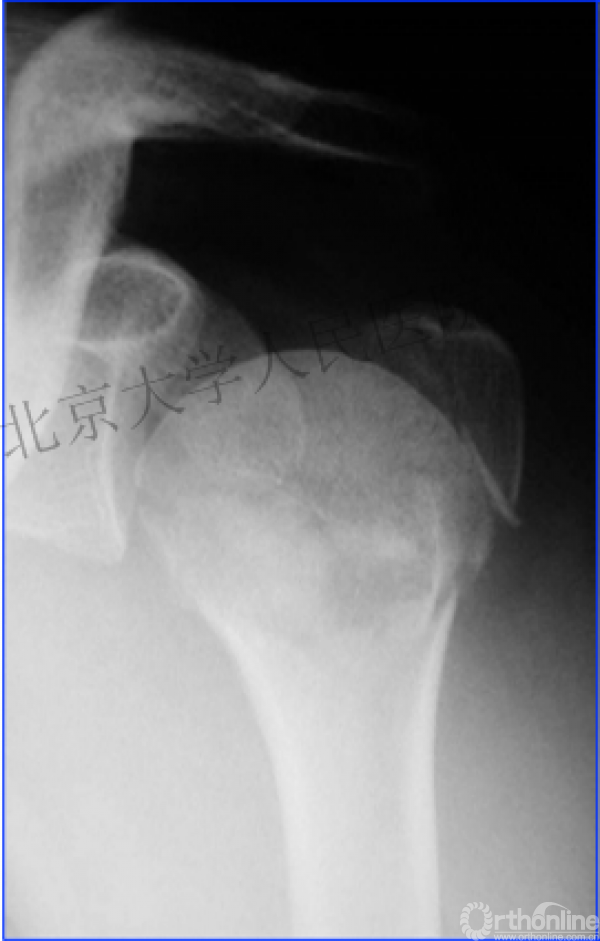

二、临床中我们常遇到类似下面的病例

内侧皮质粉碎,低位外科颈骨折,肱骨头-干角维持困难。